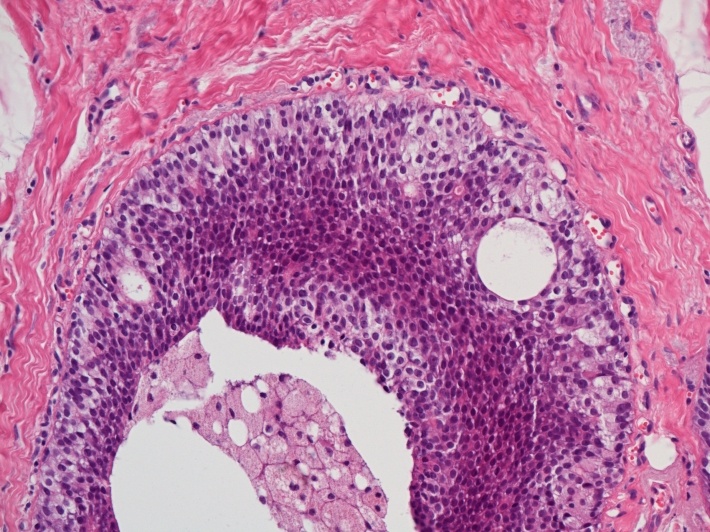

Normální prsní žláza se skládá z několika laloků, které se dále dělí do jednotlivých lalůčků. V každém lalůčku se vyskytují partie, v nichž se za normálních okolností tvoří u kojících žen mléko (tzv. aciny či lobuly) a dále větvící se strom drobných vývodů, které toto mléko odvádějí k bradavce (tzv. dukty).

Podle toho, zda nádorová tkáň napodobuje spíše buňky lobulů či duktů se rozlišují dvě základní skupiny karcinomů prsu – tzv. duktální a lobulární karcinom.

Podle toho, zda nádorové buňky již získaly schopnost prorůstání z původních lobulů či vývodů do okolní tkáně (vaziva a tuku) se rozlišují nádory neinvazivní (tzv. in situ rostoucí) a nádory invazivní.

Kombinací obou výše zmíněných kritérií pak lze rozlišit čtyři základní skupiny nádorů:

- duktální karcinom in situ,

Zatímco karcinomy rostoucí in situ nemají schopnost metastazovat a jejich hlavní nebezpečí spočívá ve vzniku lokální recidivy, invazivní karcinomy již pronikly do okolní tkáně, případně získaly přístup k lymfatickým či krevním cévám a proto existuje nebezpečí jejich metastatického šíření v těle.